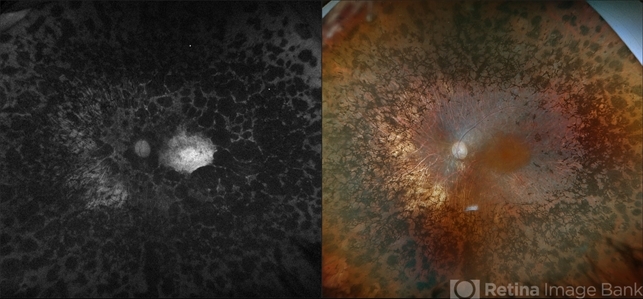

- pigmentary retinal dystrophy

- Optomap RGB and AF of the left eye of an 76-year-old woman with pigmentary retinal dystrophy. No progression of the bone spicules noted on exam and optos imaging. Will continue yearly follow care with dilated exam and optos imaging.